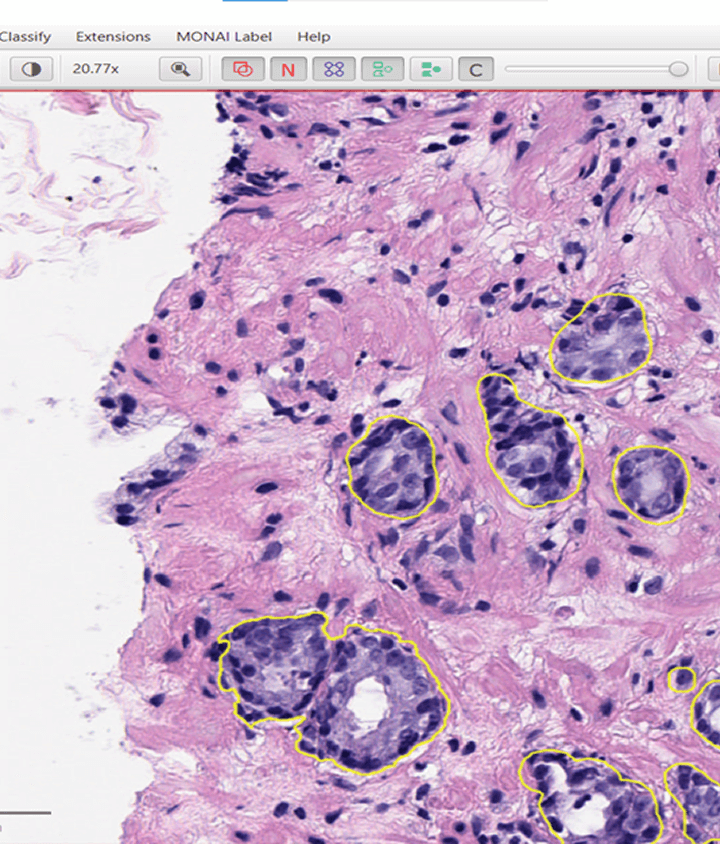

Tumor annotation on WSI H&E with Qupath platform(Breast Carcinoma)